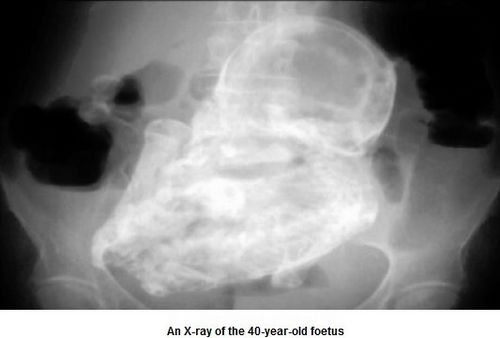

医生们通过X光透视妇女的腹部,才吃惊地发现妇女肚子里有一个已经变成化石的胎儿,医生以大小估算胎儿应该是20到28周大的时候死亡。

经X光透视,胎儿的头、四肢、肋骨和脊椎都清晰可见。医生说,四十多年来,死胎没有让这名妇女的健康出大问题,真是个奇迹。